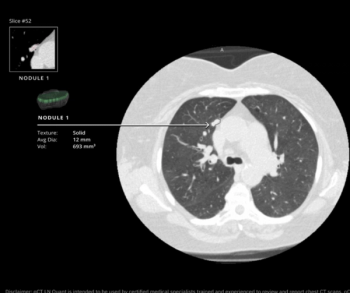

New research shows the use of adjunctive AI resulted in a 12 percent higher sensitivity rate for lung nodule detection in comparison to radiologists without AI.